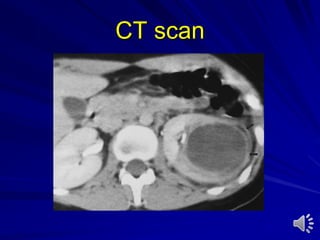

Computed tomography (CT) scan

With or without contrast medium

Indications:

– Stones

– Trauma

– Tumours

– Scaring of retroperitoneum

– Lymphadenopathy in genitourinary tumors

– Metastatic dissease